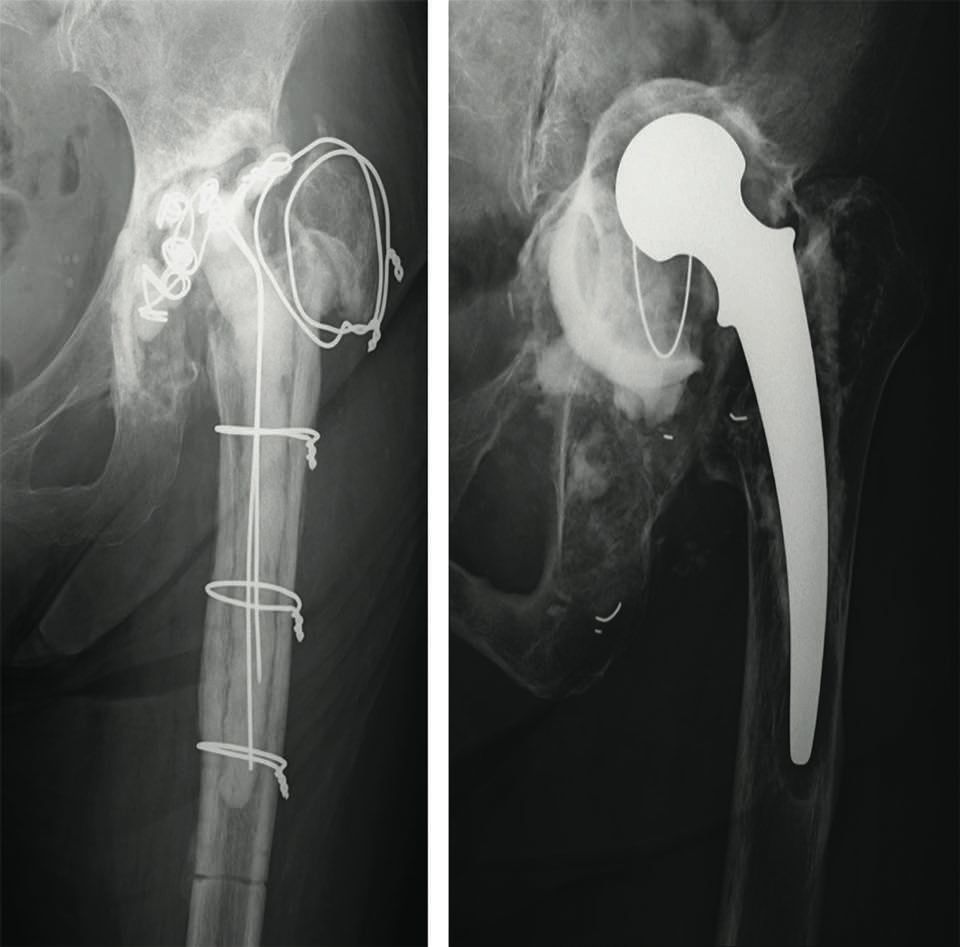

The video demonstrates the technique for reconstructing the acetabulum using an allograft and KT device (Fig. 16). It shows a two-stage revision hip replacement due to an infection. The bone defect was classified during the preoperative planning as AAOS III (combined defect).

Figures 17 and 18 show the preoperative x-rays and 3D CT images. The acetabulum was reconstructed using a KT cross and allografts.

The segmental and cavitary defects were successfully filled. Figures 19 and 20 show the postoperative images.